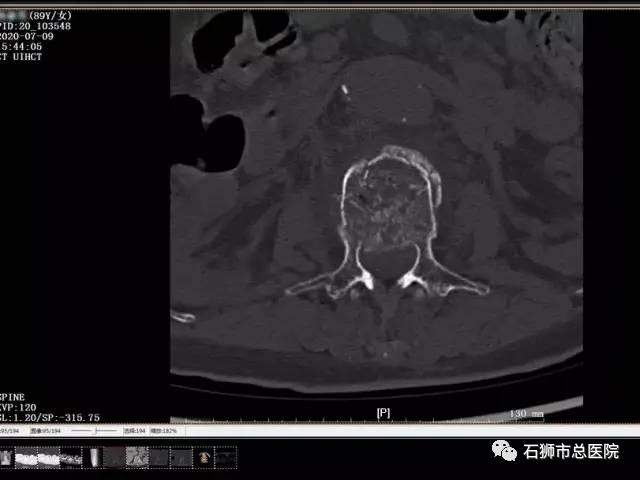

患者,女,89岁,以"摔伤致腰背部肿痛,活动受限5天"为主诉入院。入院诊断:1.腰2椎体压缩性骨折;2.骶椎骨折,3.高血压病(2级高危)。

考虑患者近九十岁高龄,常规手术风险难以耐受,且椎体后壁破碎,手术风险极高,经科室内讨论,拟行经皮椎体球囊扩张成形术,术中为进一步减少手术时间,减少手术风险,降低骨水泥经后壁进入椎管风险,予改良行单侧经皮椎体球囊扩张成形术。

术后患者恢复良好,指导功能锻炼,早期腰背支具辅助下起床活动,有效避免了患者卧床并发症的发生。

手术 · 前

手术 · 后

腰椎骨折